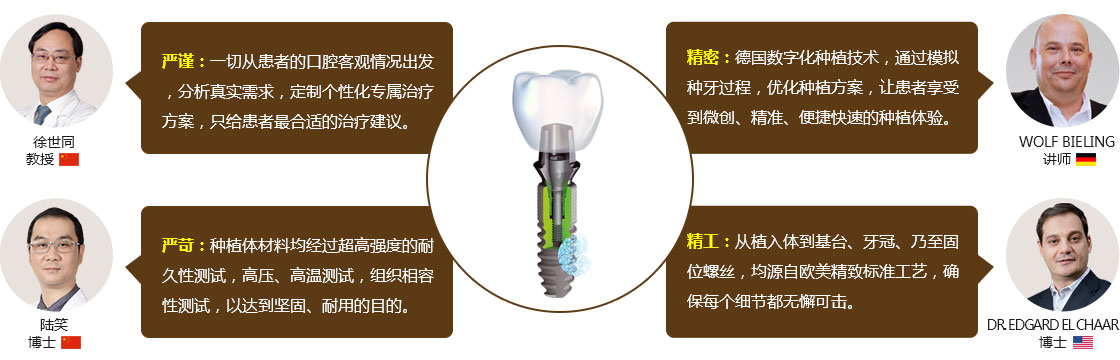

名医团 • 专家会诊研讨方案

种植手术方案由专家团联合会诊,术前、术中严格把关,安全、高效完成种牙。

20位国际种植工匠巅峰对话 见证德伦精工种植技术